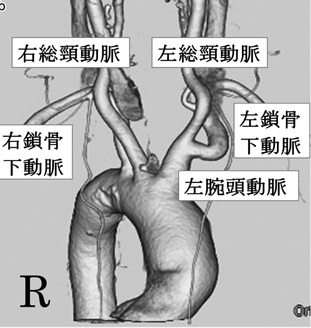

本来、右迷走神経枝は右鎖骨下動脈を、左迷走神経枝は大動脈弓を反回し、甲状腺背側を逆走します。

内臓逆位で、右大動脈弓に左鎖骨下動脈起始異常を伴い、左迷走神経枝が反回できずに左非反回下喉頭神経(nonrecurrent inferior laryngeal nerve,NRILN)になった報告があります。[Auris Nasus Larynx. 2021 Apr;48(2):317-321.][Head Neck. 2016 Oct;38(10):E2508-11.]

内臓逆位が無くても、右鎖骨下動脈起始異常などの血管走行奇形では、迷走神経が反回できず右非反回下喉頭神経(nonrecurrent inferior laryngeal nerve,NRILN)になって走行が変わるため要注意。